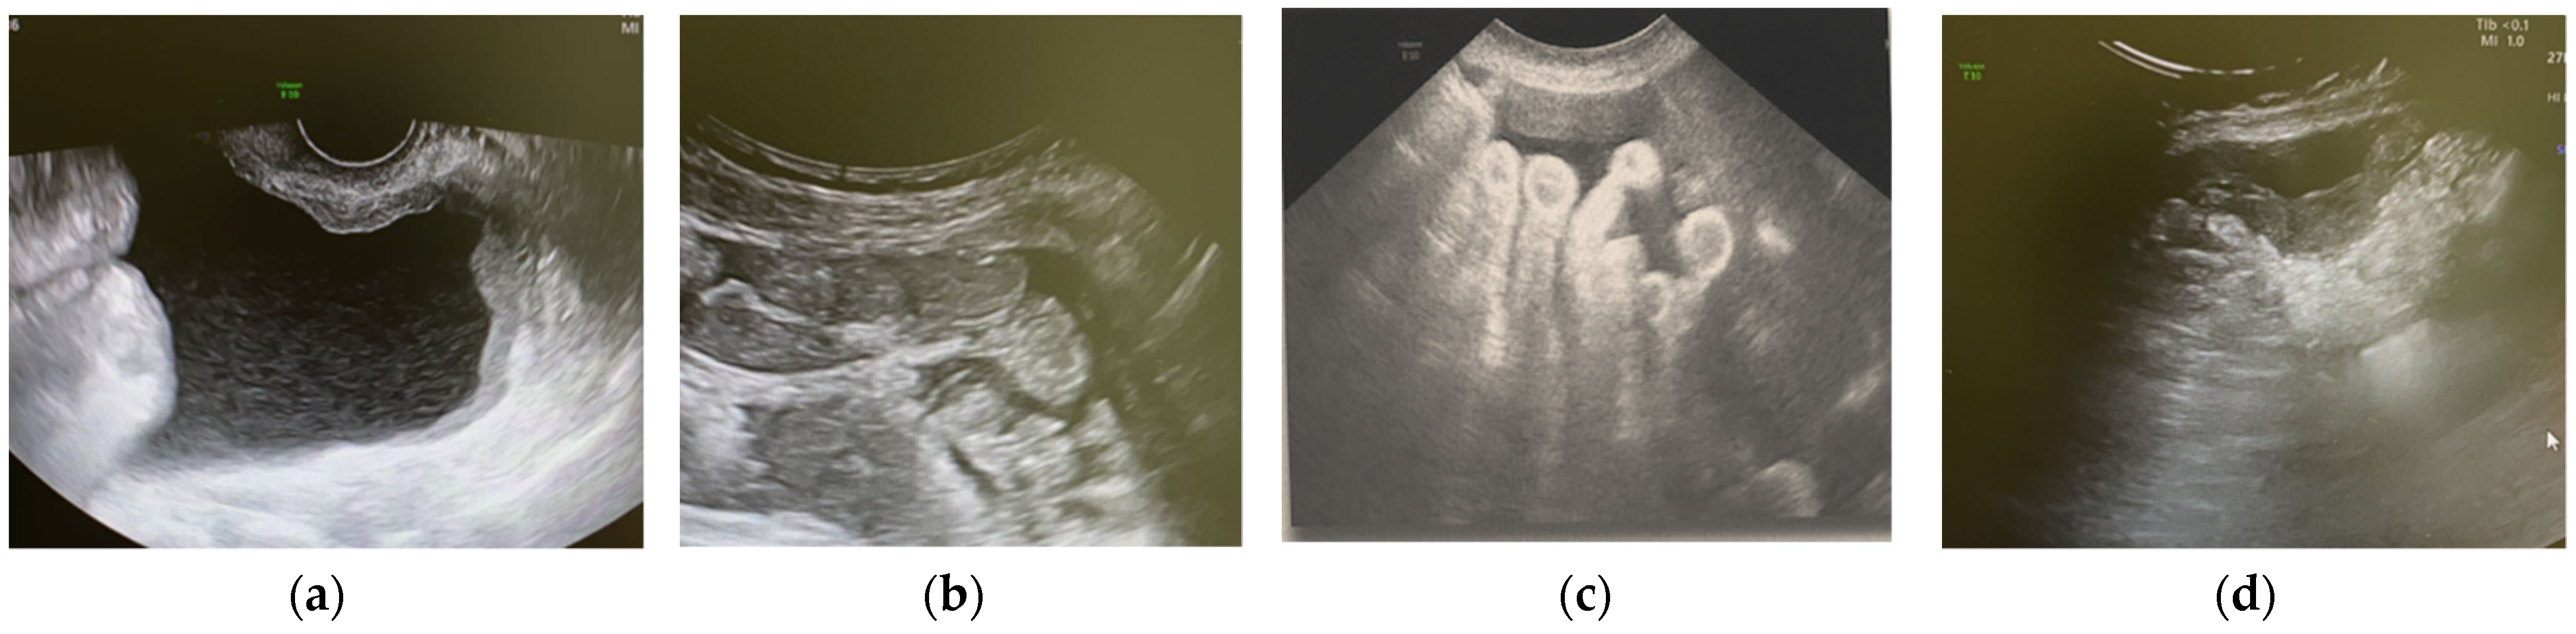

| Largest diameter of the lesion (mm): median (min-max) | 51 (8–280) |

| Type of the tumor (N, %) | |

| Solid | 34 (81%) |

| Multilocular-solid | 8 (19 %) |

| Tumor margins (N, %) | |

| Irregular | 36 (85.7%) |

| Regular | 6 (14.3%) |

| Color score (N, %) | |

| 2 | 10 (23.8%) |

| 3 | 29 (69%) |

| 4 | 3 (7.1%) |